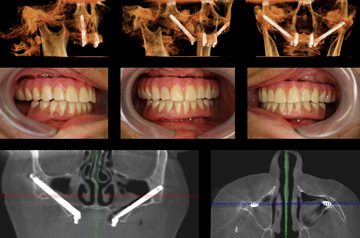

Zigoma Dental Implants

- Zygomatic implant technology

- Dental Implants Done in a Straight-Forward Procedure

- Minimal Surgical Trauma Resulting in Maximum Aesthetics